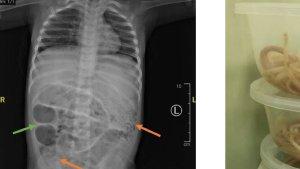

Baca juga: Dokter Kaget Setelah Lihat Isi Perut Bocah yang Membesar, Tak Bisa BAB Seminggu